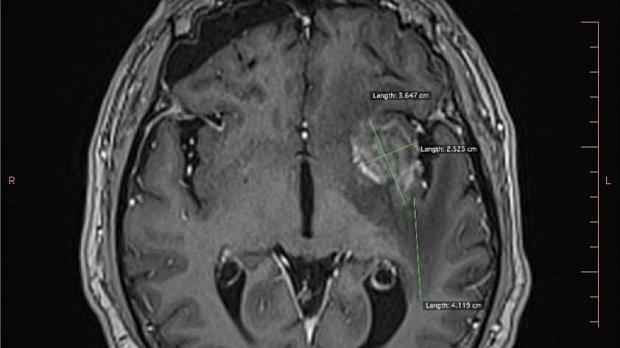

Иллюстрация №2: Рис. 2. Опухолевый очаг в левой височной доле размерами 36 х 25 мм.

По данным МРТ головного мозга от 21.03.2018г. отмечалась отрицательная динамика в виде увеличения размеров образования в левой височной доле до 36 х 25 мм, увеличения перифокального отека (рис. 2).